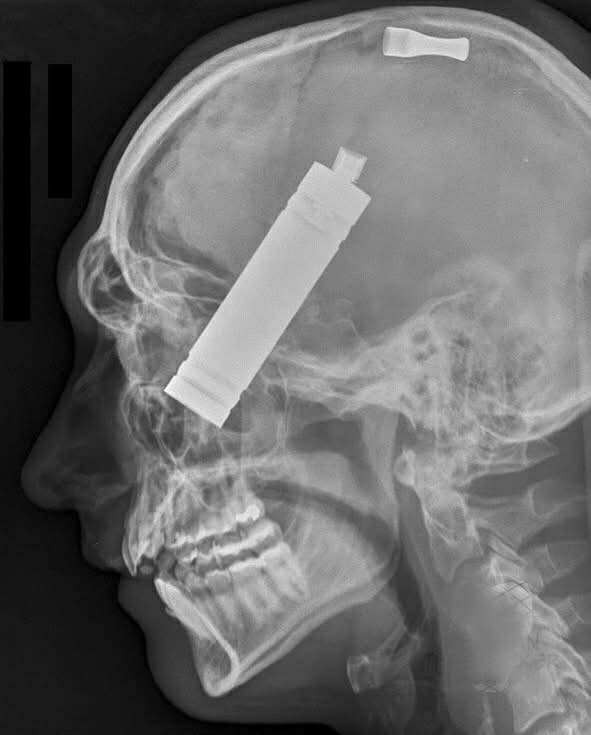

Un voisin a témoigné plus tard : « J’ai entendu une détonation, comme un coup de feu. Puis un craquement. Les flammes étaient déjà aux fenêtres.» Lorsque les pompiers ont pénétré dans la maison, la fumée était si épaisse que même les lampes torches ne pouvaient la percer. Une cigarette électronique brisée gisait sur le sol, et deux fragments de métal ont été retrouvés plus tard… dans le crâne du propriétaire.

Une radiographie a révélé que l’explosion s’était produite juste à côté de son visage. Le feu a ravagé son oreiller, ses rideaux et les murs. Selon l’autopsie, D’Elia a été brûlé sur 80 % de son corps. Il n’a même pas eu le temps de se relever. Tout s’est passé en quelques secondes.